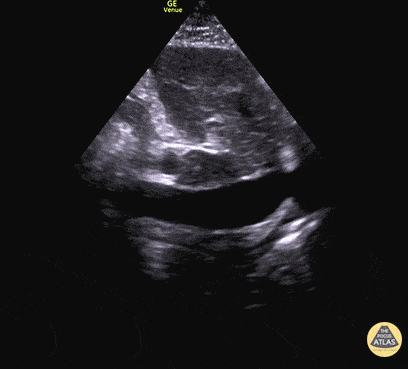

IVC & Abnormal Venous Waveforms - Plethoric IVC in Biventricular Failure

50 y/o M PMH methamphetamine abuse presents in respiratory failure with cool, mottled skin and poor capillary refill. Patient was tachycardic, hypothermic with multiple signs of end organ dysfunction. POCUS quickly narrowed the differential by demonstrating clear, severe, reduced ejection fraction by visual estimation and a plethoric IVC without respiratory variation. Patient was ultimately started on dobutamine and transferred to the MICU for treatment of cardiogenic shock. Dr. Jaclyn Walker, Dr. Matthew Riscinti - Denver Health Emergency Medicine